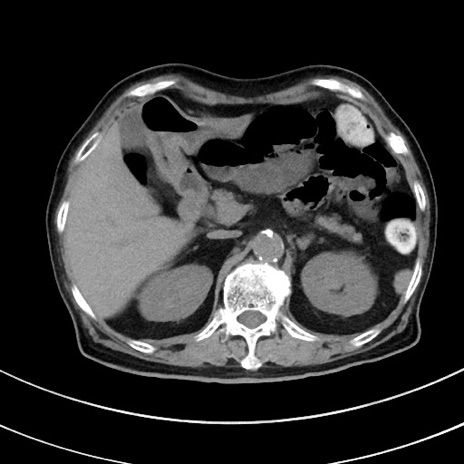

症例33(横断像)

【症例】70歳代 女性

【主訴】心窩部痛

【現病歴】延髄病変の精査・加療にて神経内科入院中。本日より心窩部痛あり。

【身体所見】右下腹部を中心に圧痛と反跳痛あり。

【データ】WBC 10900、CRP 0.02